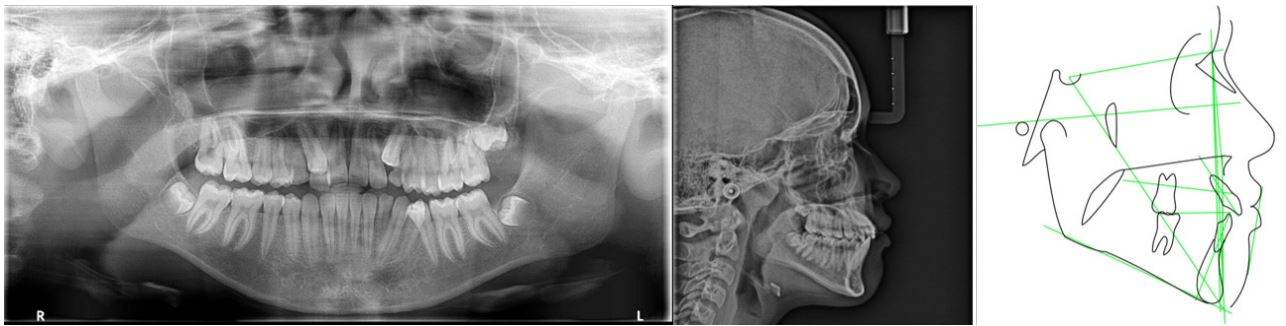

The extraoral examination revealed a slightly convex facial profile, facial asymmetry on the left side, passive lip sealing, absence of the buccal corridor when smiling. On lateral examination, closed gonial angle, lower lip located more forward than the upper lip (Figure 1).

Figure 1: Panoramic X-ray, Cephalometric X-ray and Cephalometric tracing (Source: CIMO, 2022).

In the panoramic radiograph, the contours of the floors of the right and left orbits were observed without significant alteration, well-developed maxillary sinuses, inferior nasal conchae with contours and sizes within normal limits, elements 13 and 23 are included/impacted, dental elements 28,38 and 48 are in formation, 53, 63 and 73 have prolonged retention, crowding between teeth 13/12 and 35/34. The patient’s radiography and cephalometric tracing revealed good positioning of the bone bases, configuring skeletal class I (Figure 3) and (Table 1).